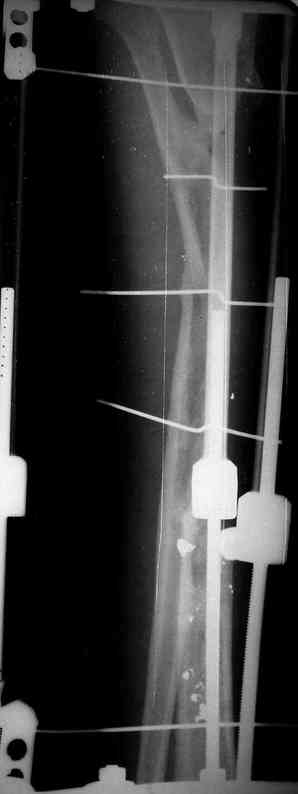

Илизарова (как придется), хирургически обработали и героически заживляли мягкие ткани с многочисленными кожными пластиками. В итоге через полгода я принял его вот таким:

Реализовал описанную выше методику, и в итоге вот что получилось. Высылаю лишь прямые проекции,

в боковых тоже всё в тему.

Очень пригодились карбоновые кольца (Джолдас -огромное спасибо, я твой должник!!!), поскольку остеопороз дистального отломка был просто невероятный. На цифровом рентгене с трудом угадывались контуры.

Рентген в процессе перемещения - внизу карбоновые кольца, тракция фрагмента спицами с упором.